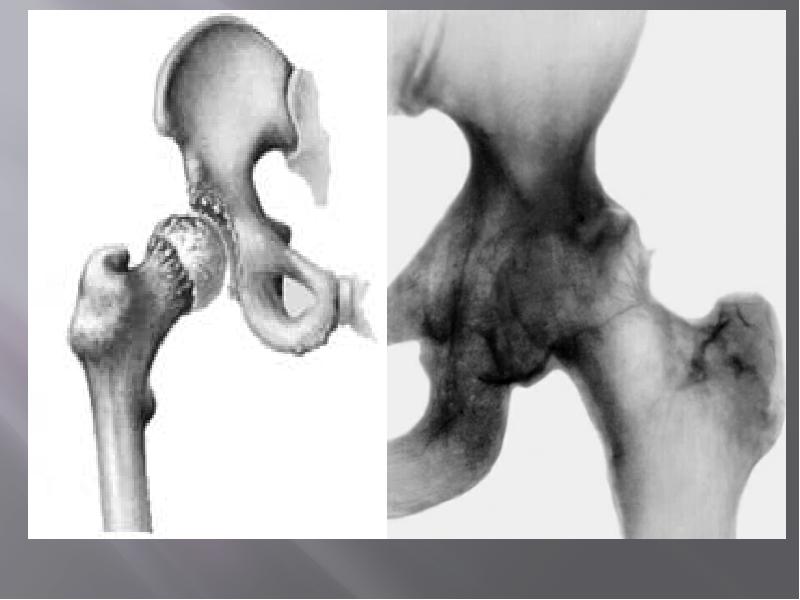

- 11. Наиболее клинически значимыми (точнее сказать, инвалидизирующими) формами деформирующего остеоартроза являются коксартроз

- 21. Рентгенологические стадии (по Келлгрену):